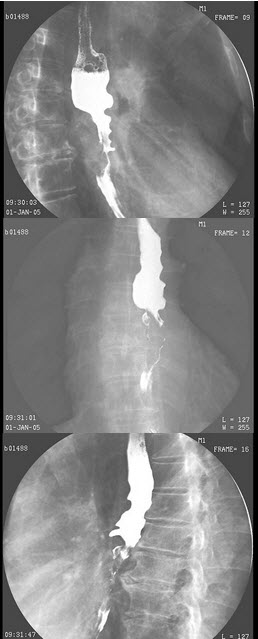

256、单项选择题

女,23岁,反复上腹部疼痛伴黑便2年余,呕吐3天。有血吸虫病史,曾行脾脏切除。结合图像,最可能的诊断为()

A.正常食管

B.食管静脉曲张

C.食管胃底静脉曲张

D.贲门失弛缓

E.食管癌

257、名词解释 腹腔脓肿